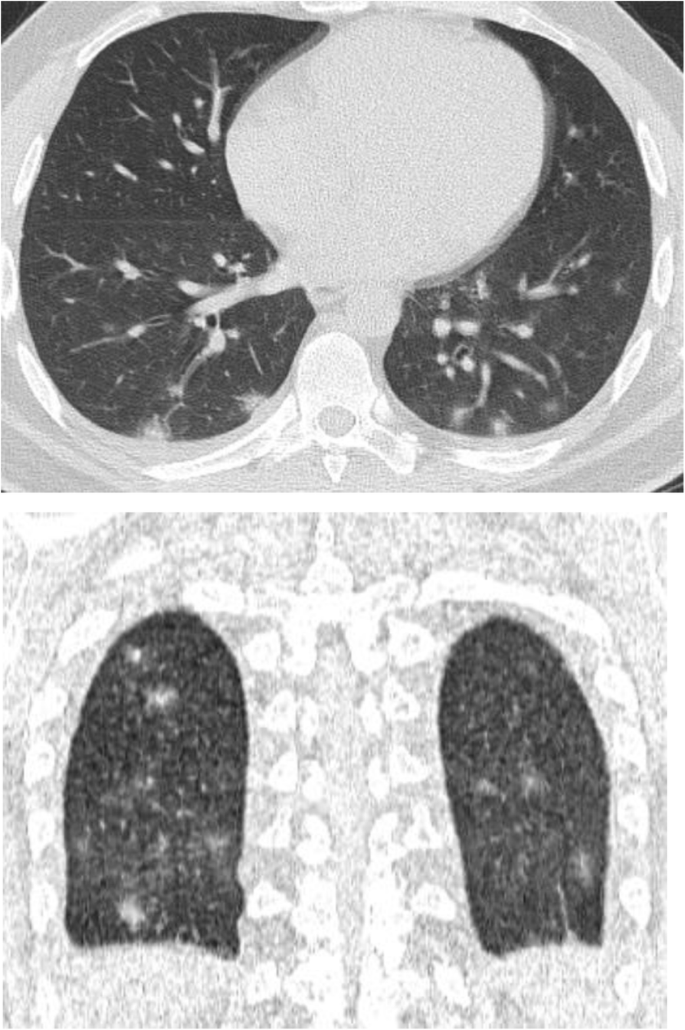

In patients with COVID-19 pneumonia, the most common findings in chest CT is GGO, which is usually described as patchy, peripheral, bilateral, and subpleural. Bao et al. [18] in a meta-analysis of 13 studies found that GGO was the most common manifestation, reported in 83.31% of cases. The meta-analysis involved 13 studies; GGO was the main finding in 11 of them. The two studies which did not report GGO were not radiological studies but were clinical studies, and they only reported bilateral abnormalities in the CT chest, and they should be excluded in our opinion [19, 20]. In another meta-analysis by Zhu et al. [21] involving 32 articles and 4121 patients, they reported ground glass opacification as the most common finding (68.1%). The relative low prevalence of GGO in this meta-analysis is because of the marked heterogeneity in the articles concerned mostly about clinical or laboratory findings. The ground glass opacification is the main CT chest findings in all articles published in radiology journal or other imaging journals [22,23,24,25,26,27,28,29,30,31,32,33,34,35,36,37,38,39,40,41,42]. For example, Guan et al. [37] in a study including 53 patients with COVID-19 reported GGO in all patients (100%). Ng et al. [15] reported 86% incidence of GGO, and the rest of the patients had GGO with consolidation. The expert recommendations from the Chinese Medical Association Radiology Branch classified the CT manifestations according to the appearance of GGO into four stages [43]; the early stage (Fig. 1) is characterized by dilatation of capillaries and engorgement of vessels, mild fluid exudates in the alveoli, and interstitial edema, resulting in single or multiple patchy ground glass opacities. The ground glass opacities are mostly peripheral and subpleural. The second stage is the advanced stage (Figs. 2 and 3) in which the lesions increase in density and size, forming mixed pattern of GGO and consolidation with or without air bronchogram. The cause of this appearance is the exudation into the alveolar space and the lung interstitium [10, 44]. The third severe stage in which there is fibrous exudates into the alveoli reflected in the chest CT as wide areas of consolidation with air bronchogram, with the non-consolidated area showing patchy ground glass infiltration (Fig. 4). In the 4th dissipation stage, the consolidation and ground glass infiltration gradually resolves, with small areas of residual fibrosis (Fig. 5). In some cases, the diffuse ground glass infiltration may give the lungs a white lung appearance (Fig. 6).

Three different cases of early COVID-19 pneumonitis. a Patient in second day after appearance of symptoms with ill-defined early ground glass infiltration patches in the left lower lobe. b Patient in third day of symptoms with multiple patchy areas of sub-pleural ground glass infiltration in both lungs. c Another patient 4 days after symptoms with bilateral wide areas of ground glass infiltration